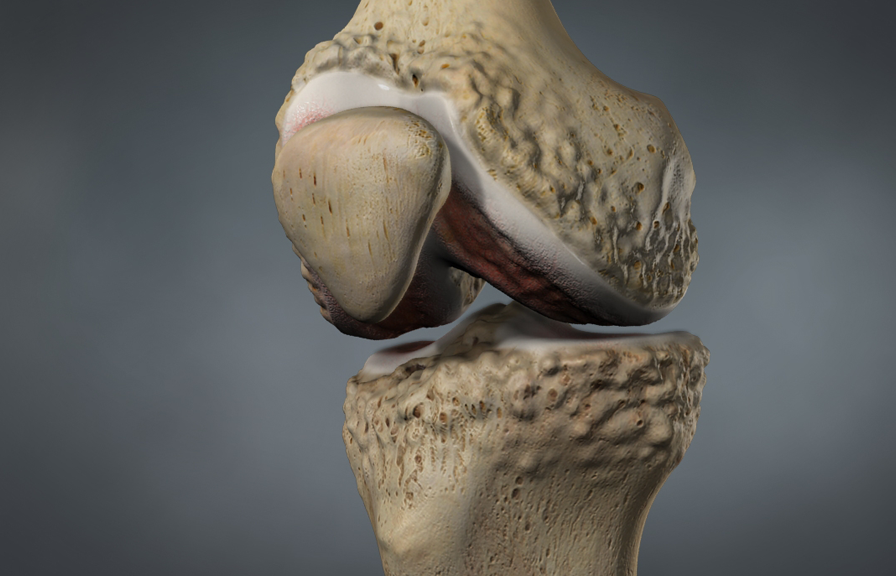

Have you had a back or neck surgery? Do you still have pain? If you suffer from chronic pain due to:

- Arthritis